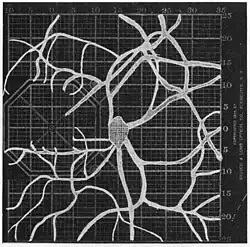

Angioscotomas were first discovered and mapped out by John Norris Evans (1891-02-28--1953-04-08)[2] in 1926, who coined the term angioscotometry to describe the painstaking charting of the scotoma of the retinal blood vessels by manual perimetry. He seated each subject in a seat in a dark setting, and tested whether they could see a tiny bright test object placed at various locations.[3] Using a 1.5 mm white disk, Evans reported intricate branch‑like scotomas that mirrored the arteries and veins emerging from the optic disc, with a full map requiring up to 2 hours to complete. He plotted this for subjects under various conditions, such as while holding breath, with glaucoma, etc. A year later, he confirmed that only short stump‑like scotomas had been noticed previously, some further data plotted with a smaller 1 mm stimuli, and under varying conditions on the subject.[4] He published a monograph on this in 1938 in which he described its use in assisting diagnosis of various conditions, such as retinal edema, glaucoma, optic neuritis, etc.[5]

In the 1940s there were further developments. Evans reviewed the state of research in 1942.[6] In 1945, Welt designed a portable campimeter and linked the size of both the blind spot and the angioscotoma to retinal arterial pressure.[7] In the same year, Weekers and Humblet published detailed tracings that overlaid vessel photographs onto Bjerrum screen plots, firmly establishing the one‑to‑one correspondence between vascular anatomy and scotoma shape.[8]

Using eccentric fixation, the more nasal parts of the angioscotoma can be plotted. -

1. Pressure on globe shows only stumps of large vessels. 2. Holding the breath causes similar effect; also 3. Holding the head low. 4. Pressure on opposite eye widens arteries and still more veins, 5. Pressure on the carotid produces no definite effect. 6. Looking thru red glass brings out finer vessels. -